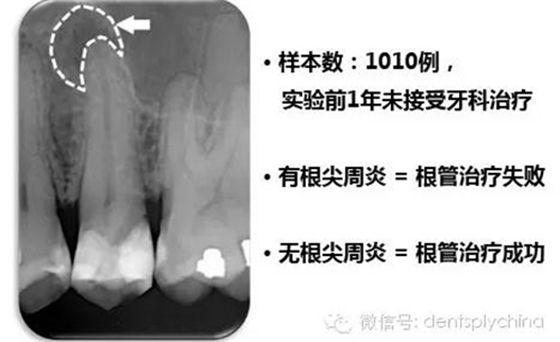

根管治療后牙齒的根尖周狀態(tài)和根管充填和冠部修復(fù)的關(guān)系

成功標(biāo)準(zhǔn): 根尖周健康 = 沒有根尖周炎

根管治療成功率和嚴(yán)密的冠部封閉密切相關(guān)

作者的結(jié)論

"對于控制根尖周感染而言,冠部修復(fù)的質(zhì)量比根管治療的質(zhì)量更重要。"